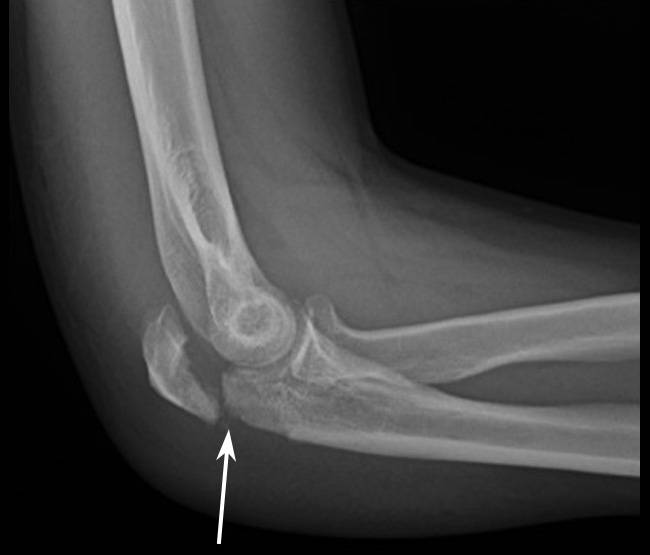

- при наличии этих симптомов, следует сделать рентгеновский снимок, подтверждающий травму

- при сложном внутрисуставном переломе рекомендуется сделать КТ

К многооскольчатым переломам можно отнести и их размозженную разновидность, когда четкая линия перелома отсутствует. На рентгенологическом снимке можно различить огромное количество мельчайших элементов кости.

Диагностика переломов локтя производится на основании результатов осмотра пострадавшего. Однако для подтверждения диагноза в обязательном порядке применяется один из видов рентгенологического обследования:

- Рентгенограмма в 2-х проекциях;

- Компьютерная томография;

- Магнитно-резонансная томография

Как правило, для окончательной постановки диагноза бывает достаточно обыкновенной рентгенографии.

Дорогостоящие методы обследования применяются только при сложных переломах, когда врачу необходимо получить трехмерное изображение поврежденного участка и установить степень повреждения окололежащих мягких тканей.